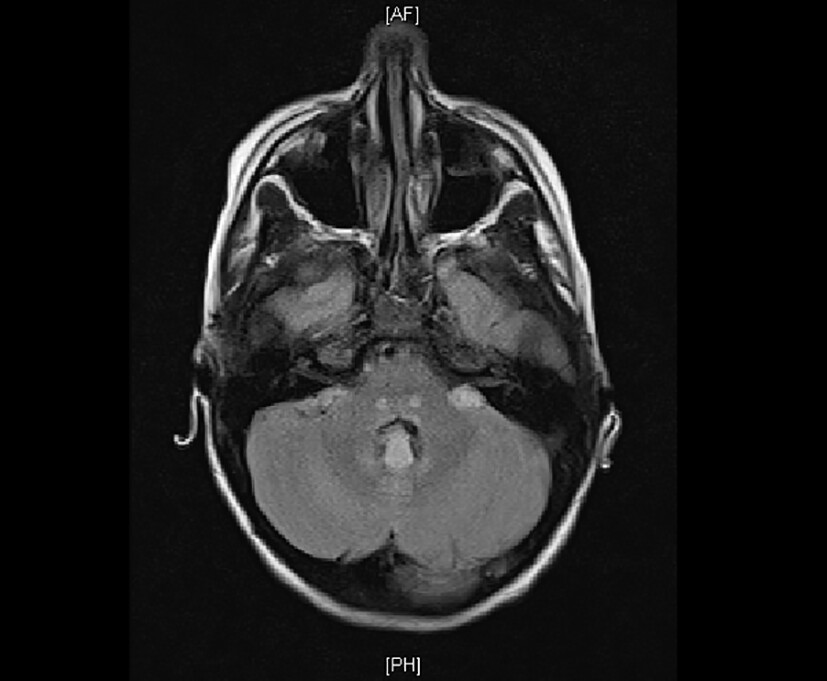

Umgehend erfolgt die Anlage eines Peritonealkatheters, um eine kontinuierliche Peritonealdialyse beginnen zu können. Die Flüssigkeitszufuhr wird beschränkt auf 400 ml/m² KOF/Tag („insensible losses“). Noch am Aufnahmeabend beklagt das Mädchen zunehmende Kopfschmerzen und Doppelbilder. Sie erscheint deutlich verwirrt und wesensgeändert. Die übrige neurologische Untersuchung und das EEG sind unauffällig. Die kranielle MR-Tomographie zeigt eine nahezu symmetrische Diffusionseinschränkung in den Basalganglien, aber keine offensichtlichen T2-Hyperintensitäten, außer im dorsalen Thalamus. Zudem sind diskrete Diffusionseinschränkungen im präzentralen Cortex erkennbar. Infratentoriell bestehen ebenfalls fast symmetrische punktförmige T2-Hyperintensitäten im dorsalen parazentralen Pons, in der Medulla oblongata und im Lobus flocculonodularis (Abb. 2). Hier ist keine Diffusionseinschränkung erkennbar. Hinweise für Blutungen, auch Mikrohämorrhagien, gibt es nicht, kein Hirnödem, unauffällige Liquorräume. Die Gefäßdarstellung und Perfusion sind unauffällig.